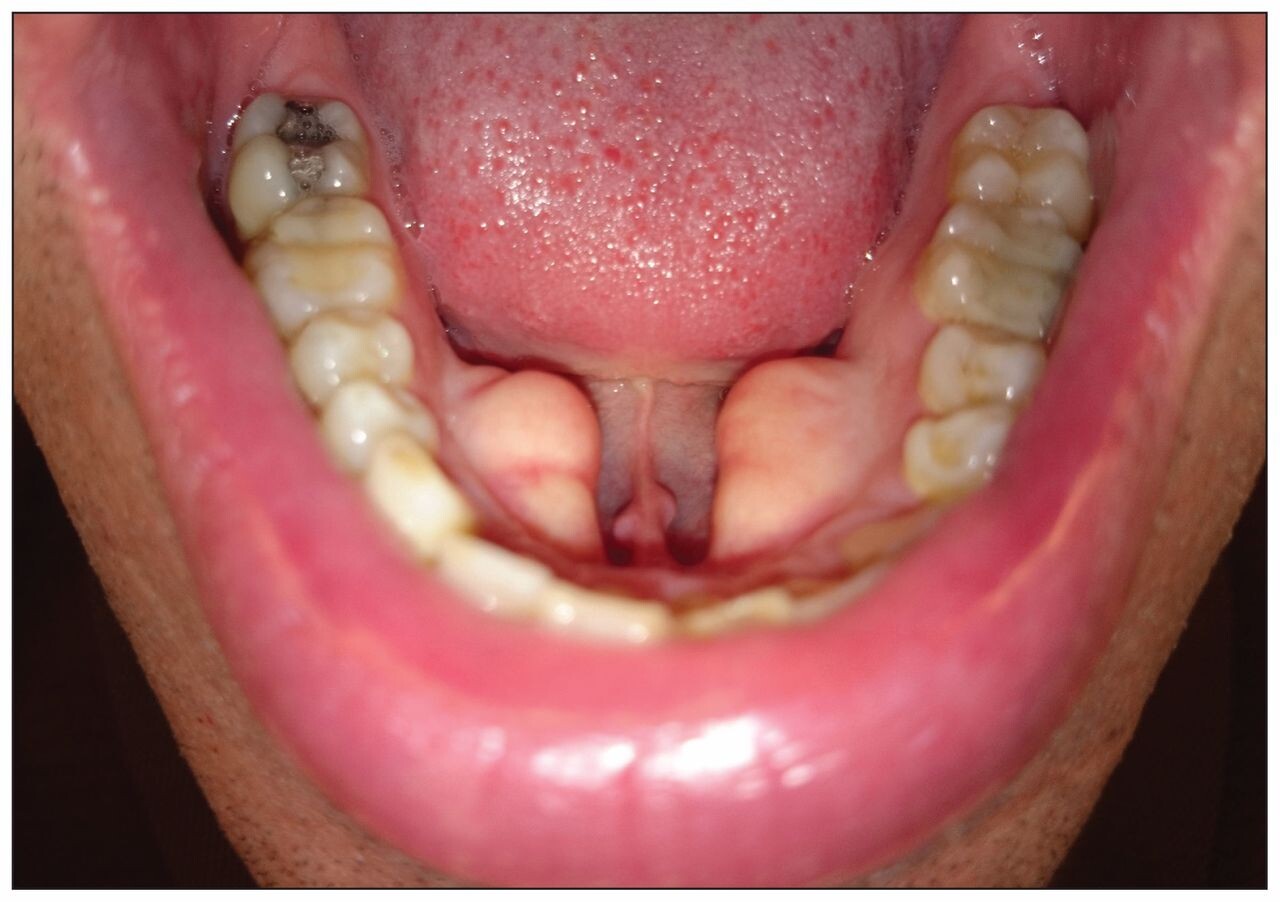

The type of exostosis you have depends on its location in your mouth. The most commonly occurring bone growths are found in the mouth's roof (torus palatinus) and beneath the tongue (torus mandibularus). Buccal exostoses are hard bony protrusions on the outside of your gums and are less common. Torus palatinus is often a singular growth, whereas torus mandibularus and buccal exostoses tend to be bilateral, meaning they happen on both sides of the mouth.

Exostoses are considered a variation of normal, and most often, they pose no health concern at all. Occasionally they can develop some adverse effects, especially if they become large enough to interfere with the functioning of your mouth. For instance, a torus mandibularus can make it difficult to speak properly if it grows to a certain size. Another potential issue is that the tissue covering bone growths is very thin and could get scratched or injured from sharp food, resulting in ulcer formation. Also, if you have missing teeth and are considering dentures, all types of exostosis can potentially interfere with the placement of your artificial teeth. Some people may want a growth removed due to aesthetic concerns.

Although these growths are benign, occasionally they can cause problems, especially if they become large enough to interfere with functions of the mouth. If very large, TM can inhibit proper speaking, and all types of exostosis can interfere with denture placement. Additionally, the mucosa covering them is very thin and prone to scratches and injuries from sharp food, sometimes resulting in ulcer formation from the trauma.